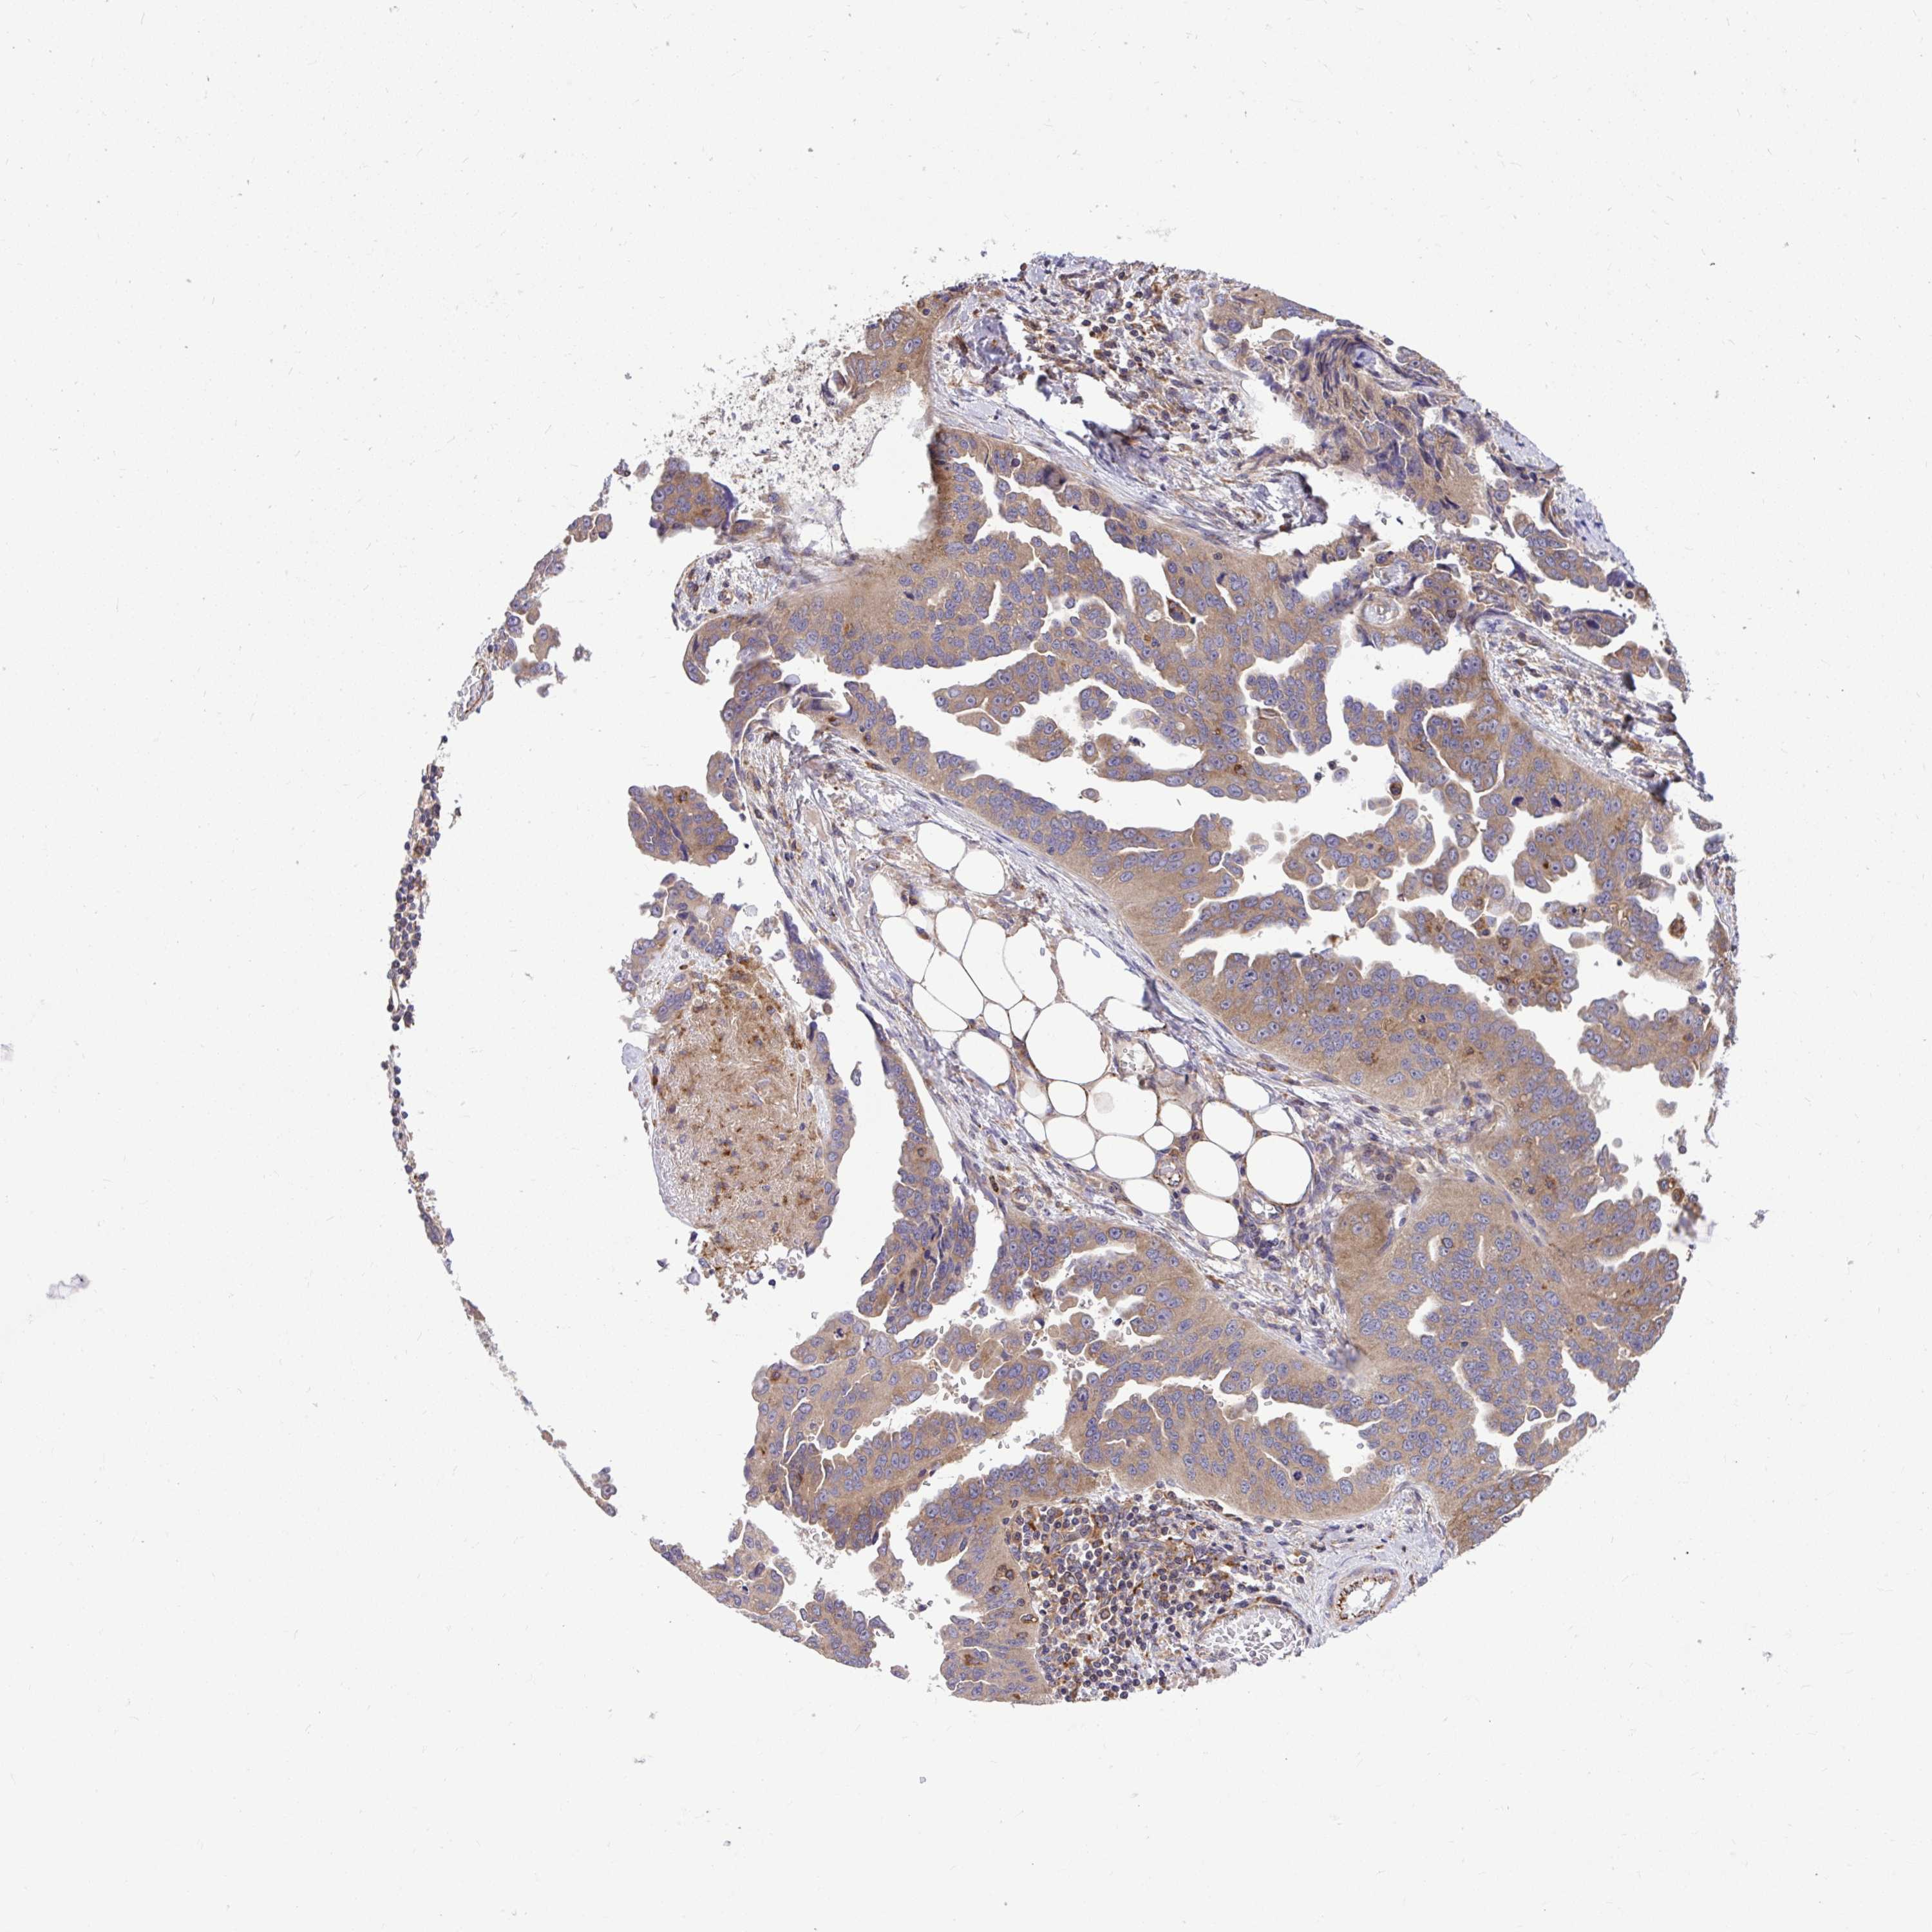

OVARIAN CANCER - Protein expressioni

A mouse-over function shows sample information and annotation data. Click on an image to view it in a full screen mode. Samples can be filtered based on level of antibody staining by selecting one or several of the following categories: high, medium, low and not detected. The assay and annotation is described here.

Note that samples used for immunohistochemistry by the Human Protein Atlas do not correspond to samples in the TCGA dataset.

Antibody stainingi

Antibody staining in the annotated cell types in the current human tissue is reported as not detected, low, medium, or high, based on conventional immunohistochemistry profiling in selected tissues. This score is based on the combination of the staining intensity and fraction of stained cells.

Each image is clickable and will lead to virtual microscopy that enables deeper exploration of all samples and also displays staining intensity scores, fraction scores and subcellular localization as well as patient and tissue information for each sample.

Antibody HPA035945

Antibody HPA056766

Antibody CAB037212

Cystadenocarcinoma, serous, NOS